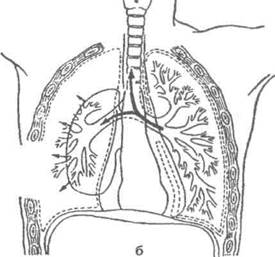

Схемы дыхания: Пневмоторакс на изображениях